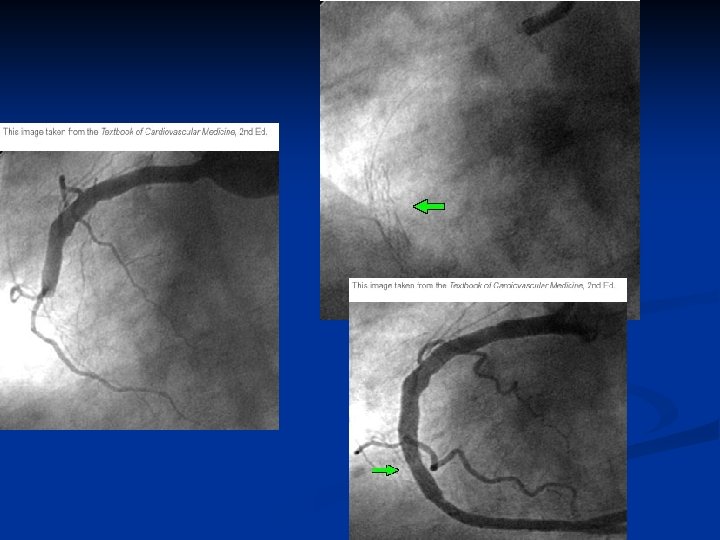

Physiopathologie de l’IDM n n n ISCHEMIE MYOCARDIQUE IRREVERSIBLE 90 % occlusion artérielle coronaire Ulcération de la plaque d’athérome et formation d’un thrombus frais NECROSE MYOCARDIQUE DEFINITIVE AKINESIE

Perméabilité coronaire et survie (1) Kleiman. Circulation. 1994; 90: 2658

Perméabilité coronaire et survie (2)